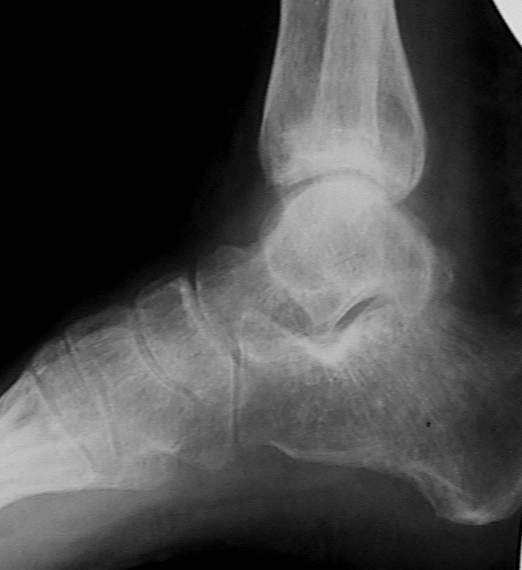

У больного травма в августе 2001 г. Лечился консервативно, Проводилась иммобилизация гипсовой лонгетой 3 мес. В последующем местное лечение. Остается контрактура боли в области наружной лодыжки. Направлен в наше отделение в конце января 2002 г Планируется костная аутопластика, остеосинтез пластиной, винтами перелома наружной лодыжки. Решается вопрос о коррекции неправильно сросшегося перелома внутренней лодыжки. Рентгенограммы: фас; профиль; план Сергей Зырянов

на снимке, кстати, срезан ее дистальный отдел, и правильность взаимоотношений с таранной костью не оценить. Если они правильные - я бы присоединился к мнению об оставлении ее покое.

А вот укорочение внутренней, похоже, привело к натяжению дельтовидной связки и гиперпрессии в медиальном отделе сустава, и уже сейчас там

видно сужение щели. Так что есть смысл обратить внимание на ортопедическую профилактику деформирующего артроза.